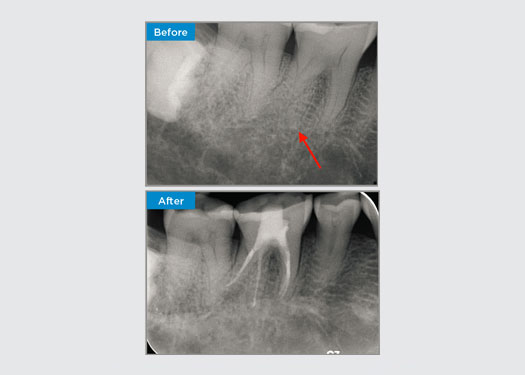

The patient presented with asymptomatic apical periodontitis on tooth 34. From the pre-op radiograph, tooth 34 was noted with two visible roots. However, a CBCT scan confirmed a three rooted premolar, and the canals divided into three at the mid root. A careful file selection is critical for this delicate tooth.

Dr Jack Lin, Endodontist, Sydney, NSW Australia

In this situation, tooth/root structure preservation is essential to reduce the risk of ledging, transportation, zipping, perforation, and root fracture. Case selection, diagnosis, and pre-treatment planning are important. Endodontic file selection with flexibility, efficiency, and respect of natural root anatomy is critical.